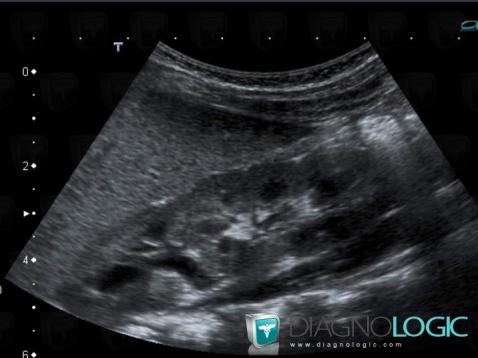

Duplication-voies excrétrices, Système collecteur, Uretère, Echographie

Voici les informations spécifiques à l'image clé ci dessus:

- Diagnostic Duplication des voies excrétrices (lié à Duplication rénale), Localisation(s) Rein, comportant les gammes Anomalie de développement rénal

- Diagnostic Duplication des voies excrétrices, Localisation(s) Uretère, comportant les gammes Système collecteur, comportant les gammes